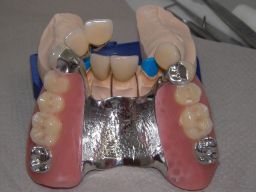

Das Hauptproblem dieses Falles lag im Oberkiefer - die über die Jahrzehnte abgeknirschten, kurzen Zähne erschweren Kronen, die durch eine Prothese belastet werden können. Die gewählte Lösung besteht darin, die Zähne nur rundherum zu beschleifen, aber nicht mehr zu kürzen und die Prothese mit einem Druckknopfsystem an die Zähne anzukoppeln, das ein "Spiel" aufweist, so daß die Prothese nicht als Hebelarm auf die schwachen Restzähne wirken kann. Rechts die beschliffenen Zähne kurz vorm Zementieren der Kronen.

Unterkiefer von vorne

Links Bilder des Oberkiefers, rechts des Unterkiefers. Die Arbeit wurde von dem Dentallabor "Heitmeyer Zahntechnik", Osnabrück, gefertigt. Dem Labor ist hier für die hervorragende Arbeit zu danken, dem Patienten für die Freigabe der Bilder!

Unterkiefer von innen

Die Zähne auf der Prothese sind aus verarbeitungstechnischen Gründen auch heute meist noch aus Kunststoff, auch wenn teurere Keramikzähne möglich wären. Kunststoff verschleißt über die Jahre, der Biß verändert sich. Um letzteres zu verhindern, sind hier zusätzlich Metallkauflächen eingearbeitet, die sich nicht verändern werden.